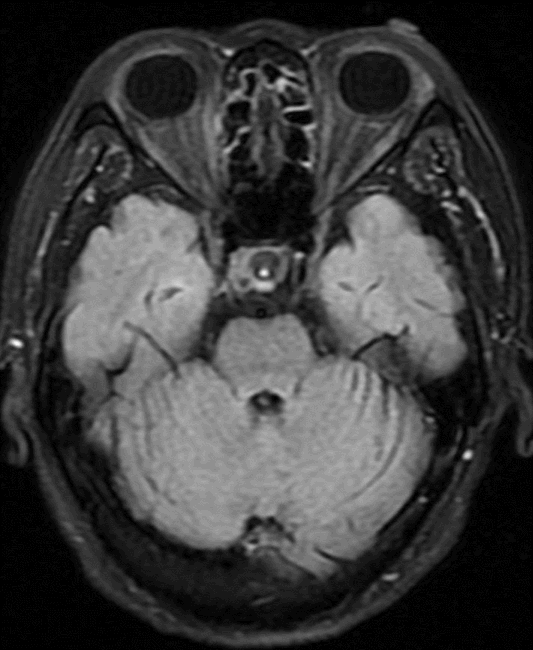

4mm×30mm Streamline

术后4月余随访:多发动脉瘤均未见显影,远端残余轻度狭窄

术前术后对比